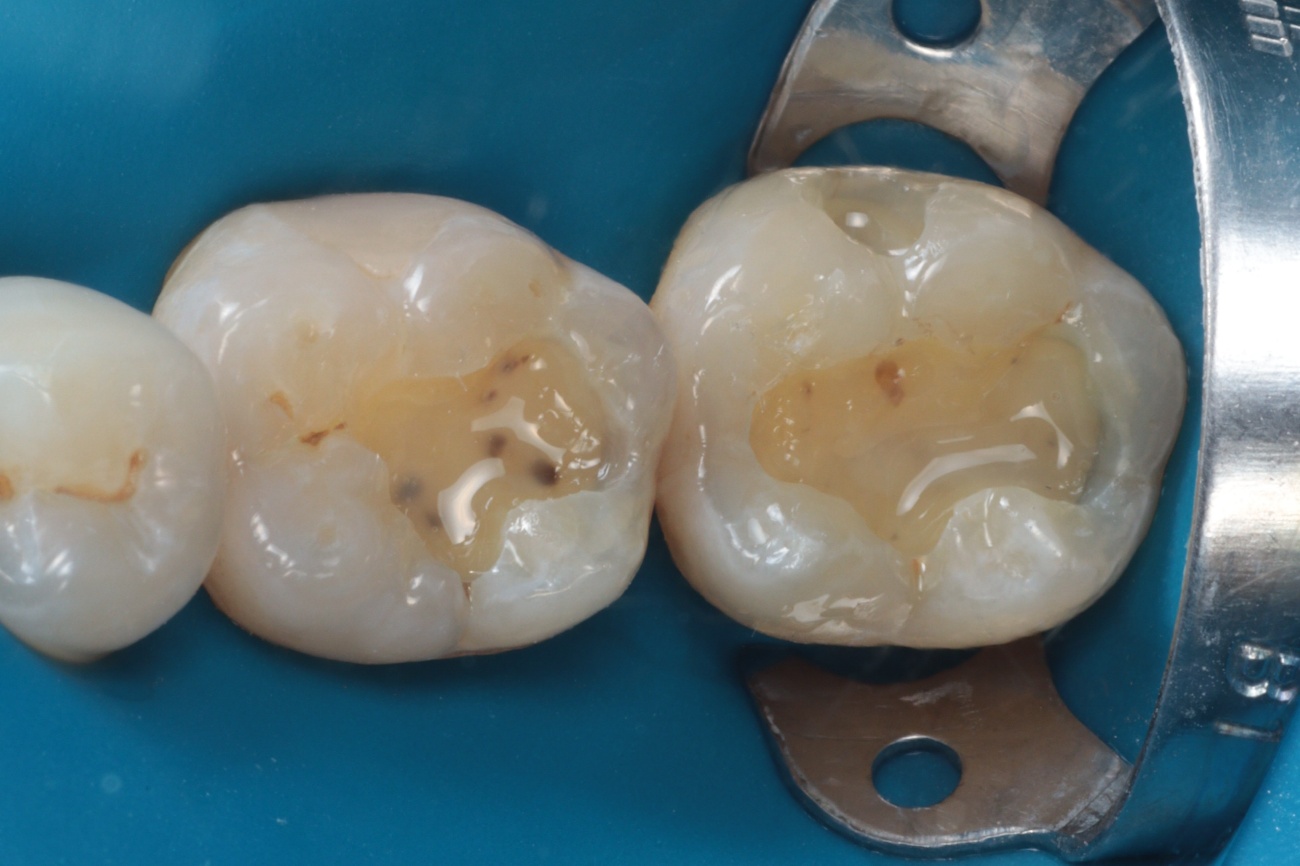

As restaurações em amálgama foram cuidadosamente removidas com brocas diamantadas em alta rotação, e a dentina comprometida foi eliminada com broca esférica carbide em baixa rotação. A cavidade foi então limpa com pedra-pomes e água para remoção de resíduos (Figura 3).

Figura 3 – Remoção do amálgama